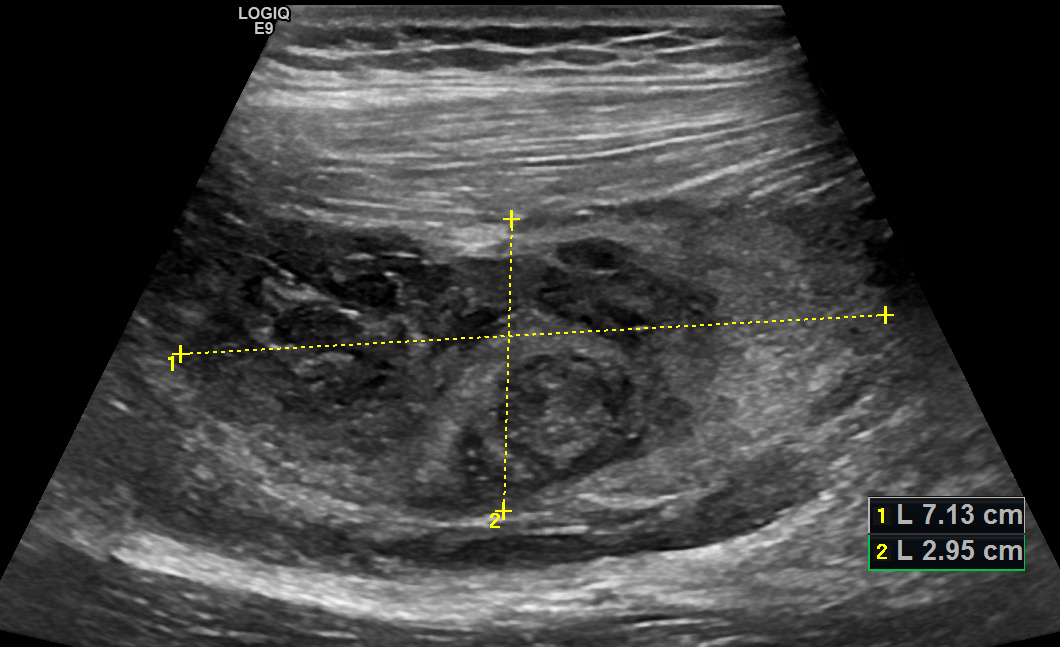

Спортсмен, 14 лет, получил травму во время тренировки. Задняя поверхность правого бедра

При ультразвуковом исследовании мягких тканей правого бедра определяется: По задней поверхности, в верхней и средней трети бедра, под длинной головкой двуглавой мышцы бедра определяется крупное скопление густой неоднородной жидкости размерами 71х46х29 мм с большим количеством плотных сгустков и нитями фибрина (свернувшаяся гематома).

Рис. 01. Межмышечная гематома, продольное сканирование

Двуглавая мышца оттеснена кнаружи и умеренно компремирована, по внутренней ее поверхности мышечные волокна видны неотчетливо.

От верхнего контура гематомы проксимально распространяется скопление густой неоднородной жидкости толщиной слоя до 8 мм шириной до 33 мм, вклинивающееся между головкой бицепса и полусухожильной мышцей и распространяющееся проксимально до подъягодичной складки.

Заключение: УЗ признаки повреждения двуглавой мышцы правого бедра с развитием крупной межмышечной гематомы.